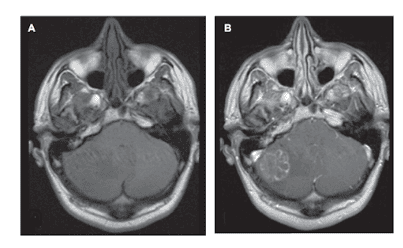

Hầu hết các di căn đầu tiên được phát hiện trên CT sọ não không tiêm thuốc cản quang, được chỉ định khi bệnh nhân có triệu chứng. Tuy nhiên, CT sọ não có độ nhạy thấp đối với di căn não và nhiều di căn bị bỏ sót. Ngoài ra, CT không cản quang có độ đặc hiệu thấp vì nhiều tổn thương khác có thể có hình ảnh tương tự. Do đó hầu hết bệnh nhân sẽ được chụp MRI não. Tuy nhiên, một số bệnh nhân chống chỉ định chụp MRI, lúc đó CT có và không có cản quang thường được chỉ định. Ngay cả với CT sọ não có thuốc cản quang, các u di căn nhỏ có thể bị bỏ sót.

MRI là kỹ thuật chẩn đoán hình ảnh tốt nhất để đánh giá di căn não. MRI não được chụp với mục đích chẩn đoán và cả lập kế hoạch điều trị. MRI có độ phân giải cao được sử dụng cho hệ thống định vị trong quá trình phẫu thuật và xạ trị. MRI chức năng (fMRI) đo sự thay đổi lưu lượng máu khi bệnh nhân thực hiện các động tác và lời nói để xác định vùng não chức năng. Qua đó xác định sự tương quan của u với các vùng não chức năng quan trọng, ví dụ vùng vỏ não chi phối vận động. Đây là thông tin rất cần thiết để hạn chế tối đa các khiếm khuyết thần kinh khi mổ bóc u.